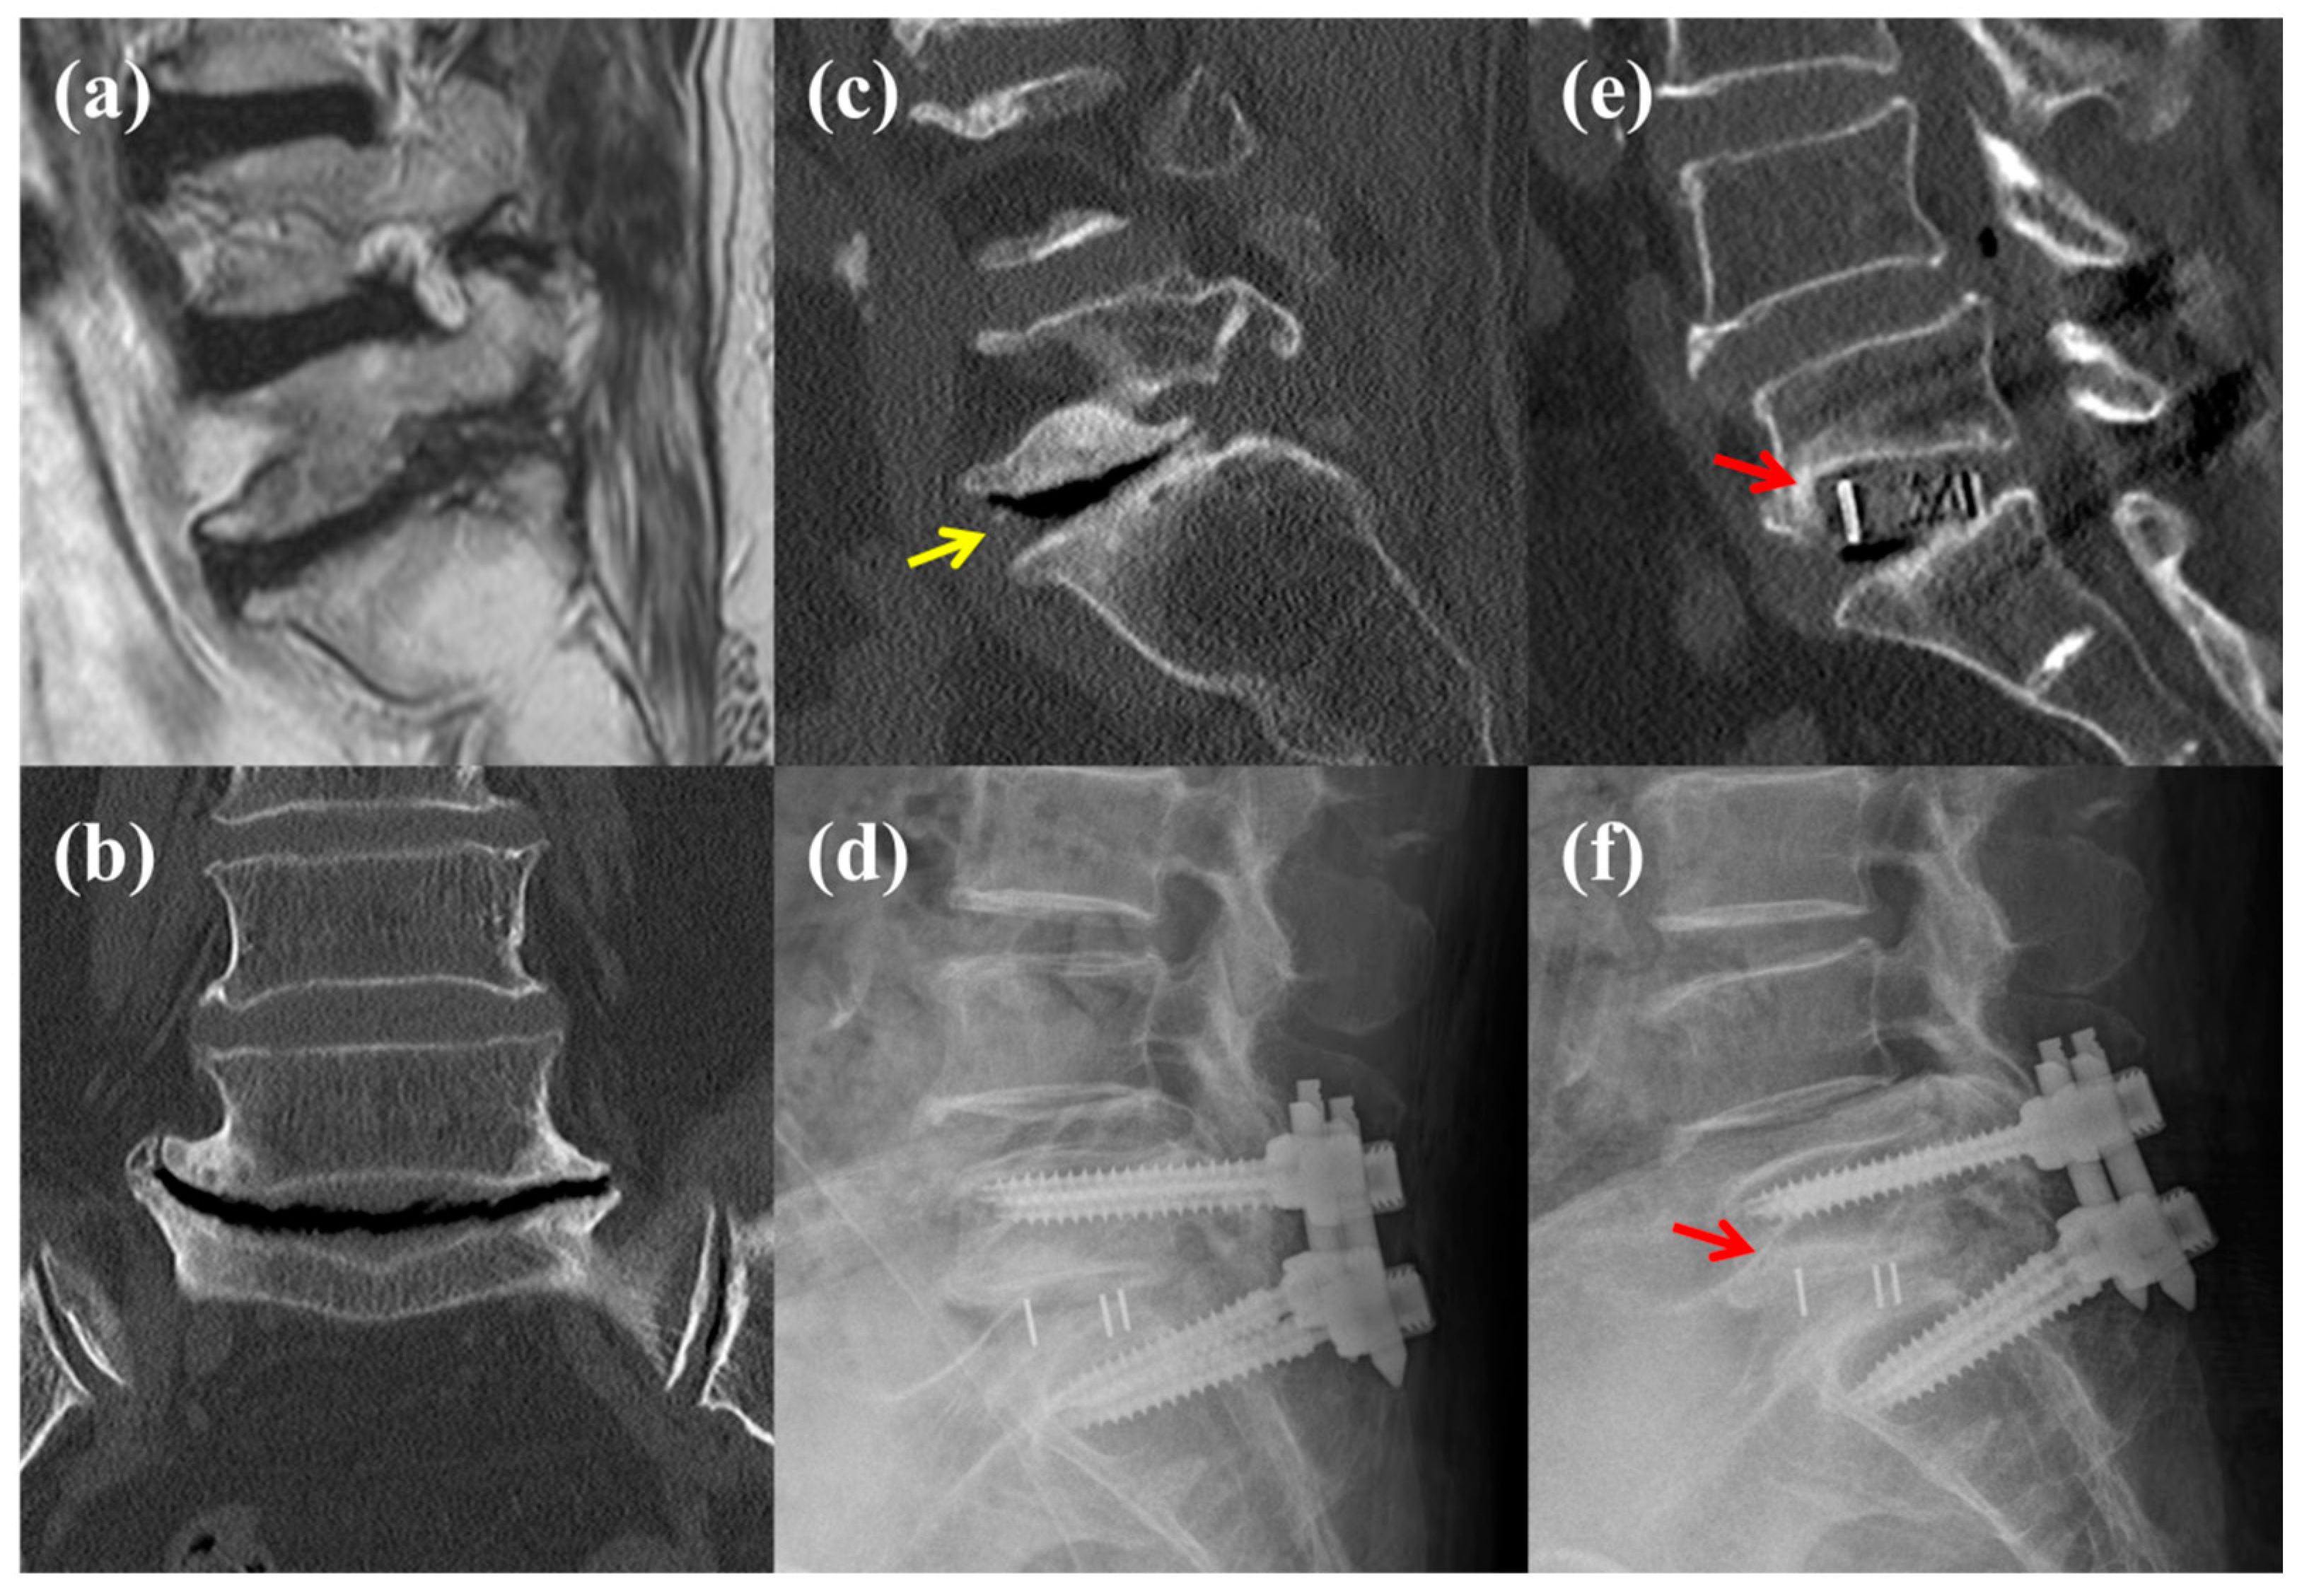

2.3. Data Collection and Radiologic Assessments